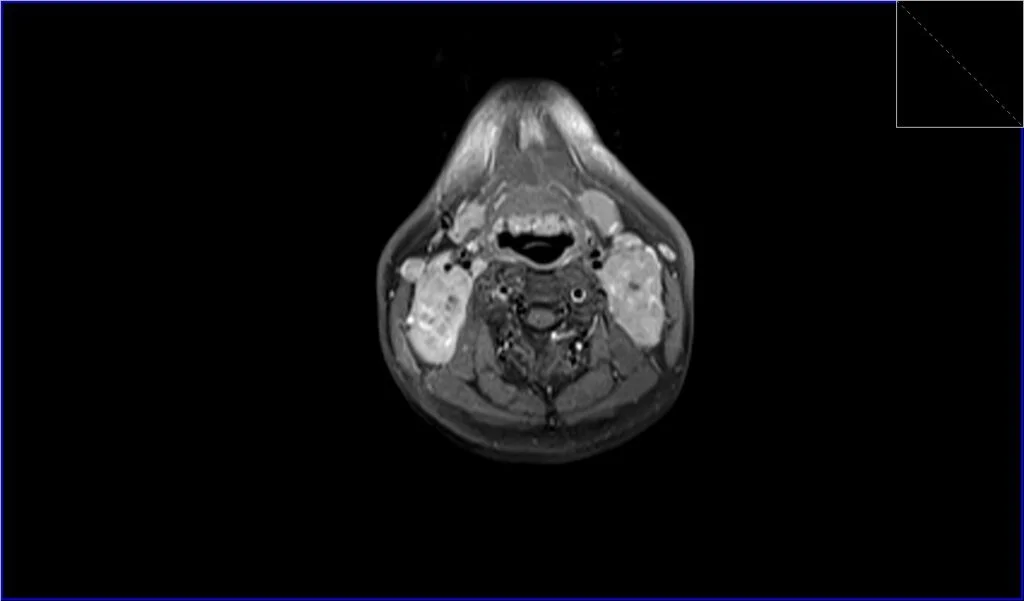

T1-Weighted Images (T1): On T1-weighted MRI sequences, lymphoma typically appears as a mass with intermediate to low signal intensity, which means it’s generally darker than the surrounding fat and lighter than the muscles.

Post-Contrast T1 Images: After the administration of a gadolinium-based contrast agent, lymphomatous nodes will typically enhance on post-contrast images. However, the enhancement pattern may be variable. Homogeneous enhancement can be seen, but sometimes there is heterogeneous enhancement, particularly in large or necrotic nodes. Post-contrast sequences are particularly useful in defining the extent of the disease and in evaluating the response to treatment.

T1 fat sat post contrast axial image shows Lymphoma